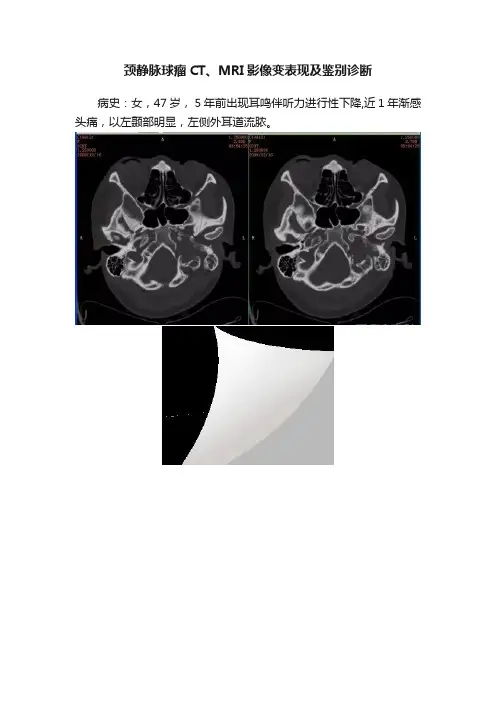

颈静脉球瘤CT、MRI影像变表现及鉴别诊断病史:女,47岁, 5年前出现耳鸣伴听力进行性下降,近1年渐感头痛,以左颞部明显,左侧外耳道流脓。